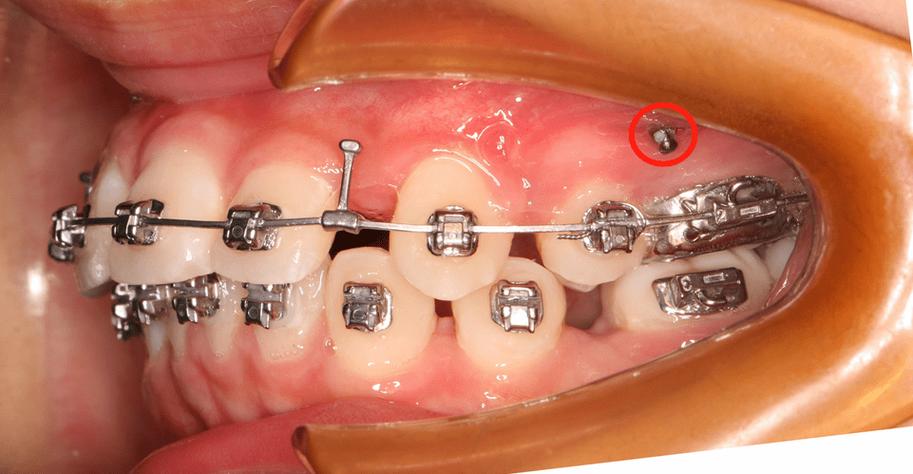

部分患者前牙前突严重,需将门牙大幅向后移动,若仅依赖后牙作支抗,后牙可能向前移位(“支抗丧失”),导致矫正效果打折扣,此时在牙槽骨中植入骨钉,可提供稳定支抗,确保前牙精准内收,同时防止后牙前移。

- 露龈笑:患者微笑时上前牙牙龈暴露过多,需压低上前牙牙冠,骨钉可固定在牙槽骨上方,直接向上施加力量,精准压低上前牙,避免其他牙齿干扰;